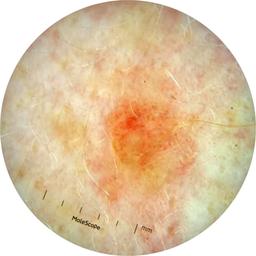

anatom_site_1 Head and neck

anatom_site_general head/neck

diagnosis_1 Malignant

diagnosis_2 Malignant adnexal epithelial proliferations - Follicular

diagnosis_3 Basal cell carcinoma

diagnosis_confirm_type single image expert consensus

fitzpatrick_skin_type I

image_type dermoscopic